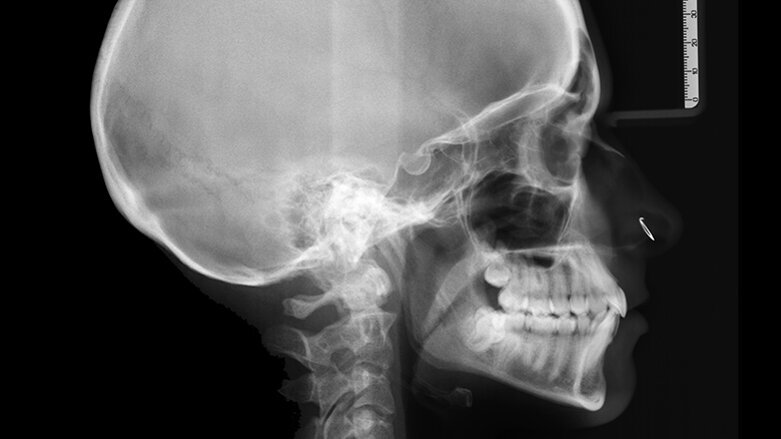

Na rentgenu se ukázalo, že struktura a morfologie kořenů je normální. V místě extrahovaného zubu 38 byly nalezeny pozůstatky kořene (obr. 2). Kefalometrická analýza odhalila I. třídu skeletálního modelu s lehce zvýšenou proklinací horních a dolních špičáků (obr. 3).